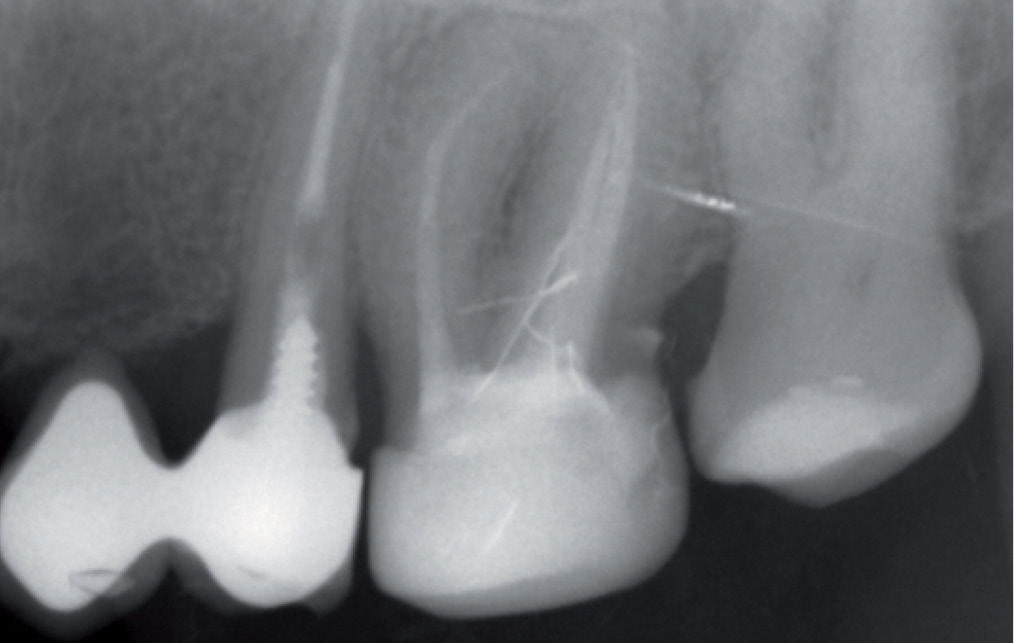

Streszczenie: Celem właściwie pojmowanego interdyscyplinarnego postępowania stomatologicznego jest przede wszystkim poprawa stanu zdrowia jamy ustnej pacjenta i wyleczenie problemów kompleksowo, nie jedynie z poziomu pojedynczej próchnicy, czyli popularnej „dziury w zębie”. Takie postępowanie wymaga od wszystkich lekarzy uczestniczących w procesie leczniczym pacjenta dobrej komunikacji, aby uniknąć błędów, które mogą być dla pacjenta niekorzystne. W publikacji przedstawiono przypadek pacjentki, która wymagała interdyscyplinarnego leczenia i nowego planu protetycznego, a nie pojedynczej endodoncji z ostatecznie błędnie zacementowanym starym uzupełnieniem protetycznym.

Summary: The aim of the proper comprehensive treatment in dentistry is a rehabilitation of oral cavity health, and interdysciplinary approach to patients needs, not only „drilling” one isolated cavity. This treatment challenges in good communication of all doctors engaged in it, to avoid the unfavorable mistakes. In publication, there is presented the case of an interdisciplinary patient who required the new prothetic plan, not only a single endodontic treatment, finally – because of the mistake in communication the reconstraction of the treated tooth was restored in not proper way.